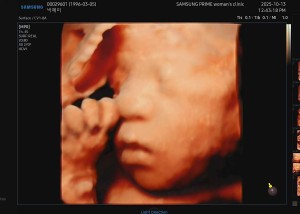

초음파사진 28주차 또쿵이에요^^

닉네임_한*혜_66

2025-10-11